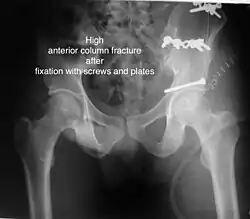

Anterior column This fracture is uncommon, typically occurring when the injuring force is applied from the side, against the greater trochanter of the femur bone, as in a fall on the side or being hit on the side. Depending on the location, the fractures are described as very low, low, intermediate and high anterior column fracture. Anterior column + posterior hemi transverse In this variety of fractures, the posterior or ilio ischial column is broken as a transverse fracture, while the anterior or ilio pubic column is broken into multiple pieces. Part of the weight-bearing dome in this variety of fractures is still attached to that part of the iliac wing, which forms part of the iliac joint. This type of injury has to be differentiated from both column fractures, where the weight-bearing dome is a floating piece not attached directly to the bone-forming sacroiliac joint.

Typically, it is caused by a combination of forces acting on the hip through the femoral head. All three X-ray views plus a CT scan are a must for the diagnosis and management of this complex injury. In this injury, non-operative treatment rarely gives satisfactory results. Surgical management is ideal. The choice of approach rests with the surgeon but going from the front or anterior approach is necessary. The posterior injury may be tacked with the anterior approach by an experienced surgeon. If the patient is unfit to undergo major surgery due to any reason, longitudinal traction to achieve secondary congruence of the hip may help to restore hip function, though partially.

The final management depends on the size of the fragment(s), stability and congruence of the joint. In some cases traction for six to eight weeks may be the only treatment required; however, surgical fixation using screw(s) and plate(s) may be required if the injury is more complex. The latter treatment will be called for if bone fragments do not fall into place, or if they are found in the joint, or if the joint itself is unstable.

• Ili inguinal, Ilio femoral of modified stoppa's approach for anterior or combined injuries